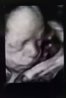

A tutaj jedno z dwóch wczorajszych zdjęć naszej pociechy

Tak się poskładała, że nóżkę miała przy brodzie

Aaa i jest już ustawiona główką w dół